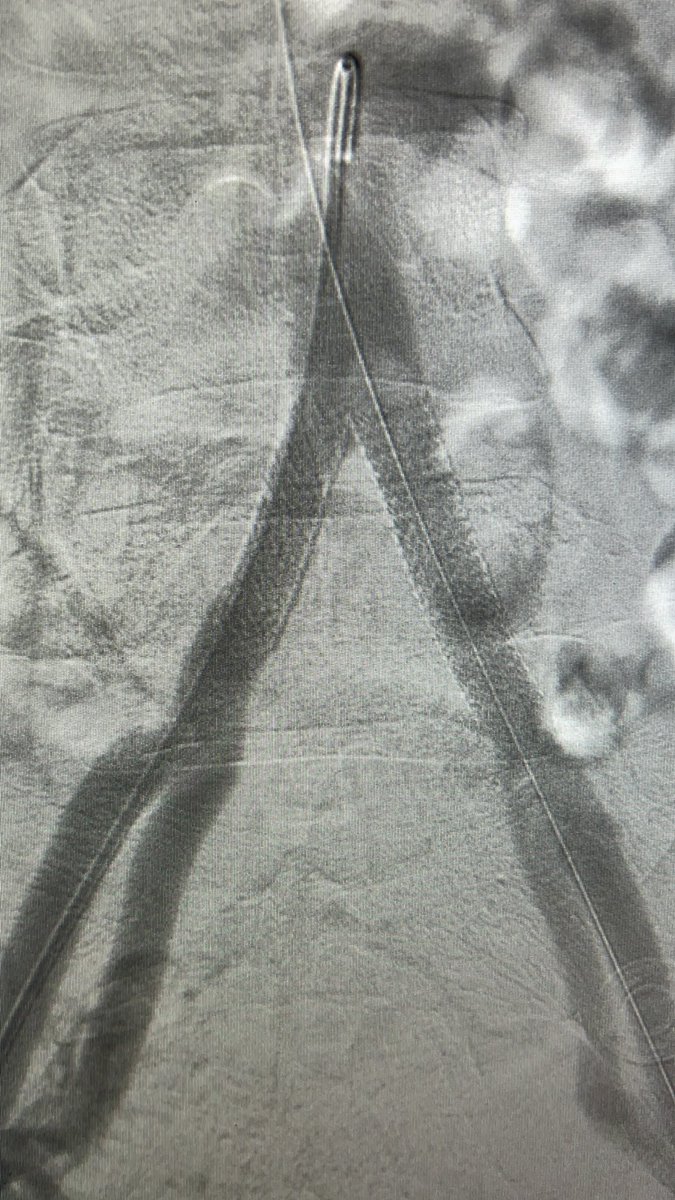

45y male CLI with CAD & hx of CABG POBA of rt SFA, retrograde crossing of lt CIA by balloon supported Command 0.018 gw, bilateral kissing bare metal BES Restoration of pedal pulses #vascular Fórum Vascular CLI Global Society #CLIFighter #endovascular

45y male CLI with CAD &amp; hx of CABG

POBA of rt SFA, retrograde crossing of lt CIA by balloon supported Command 0.018 gw, bilateral kissing bare metal BES

Restoration of pedal pulses

#vascular <a href="/VascularForum/">Fórum Vascular</a> <a href="/CLI_Global/">CLI Global Society</a> #CLIFighter #endovascular